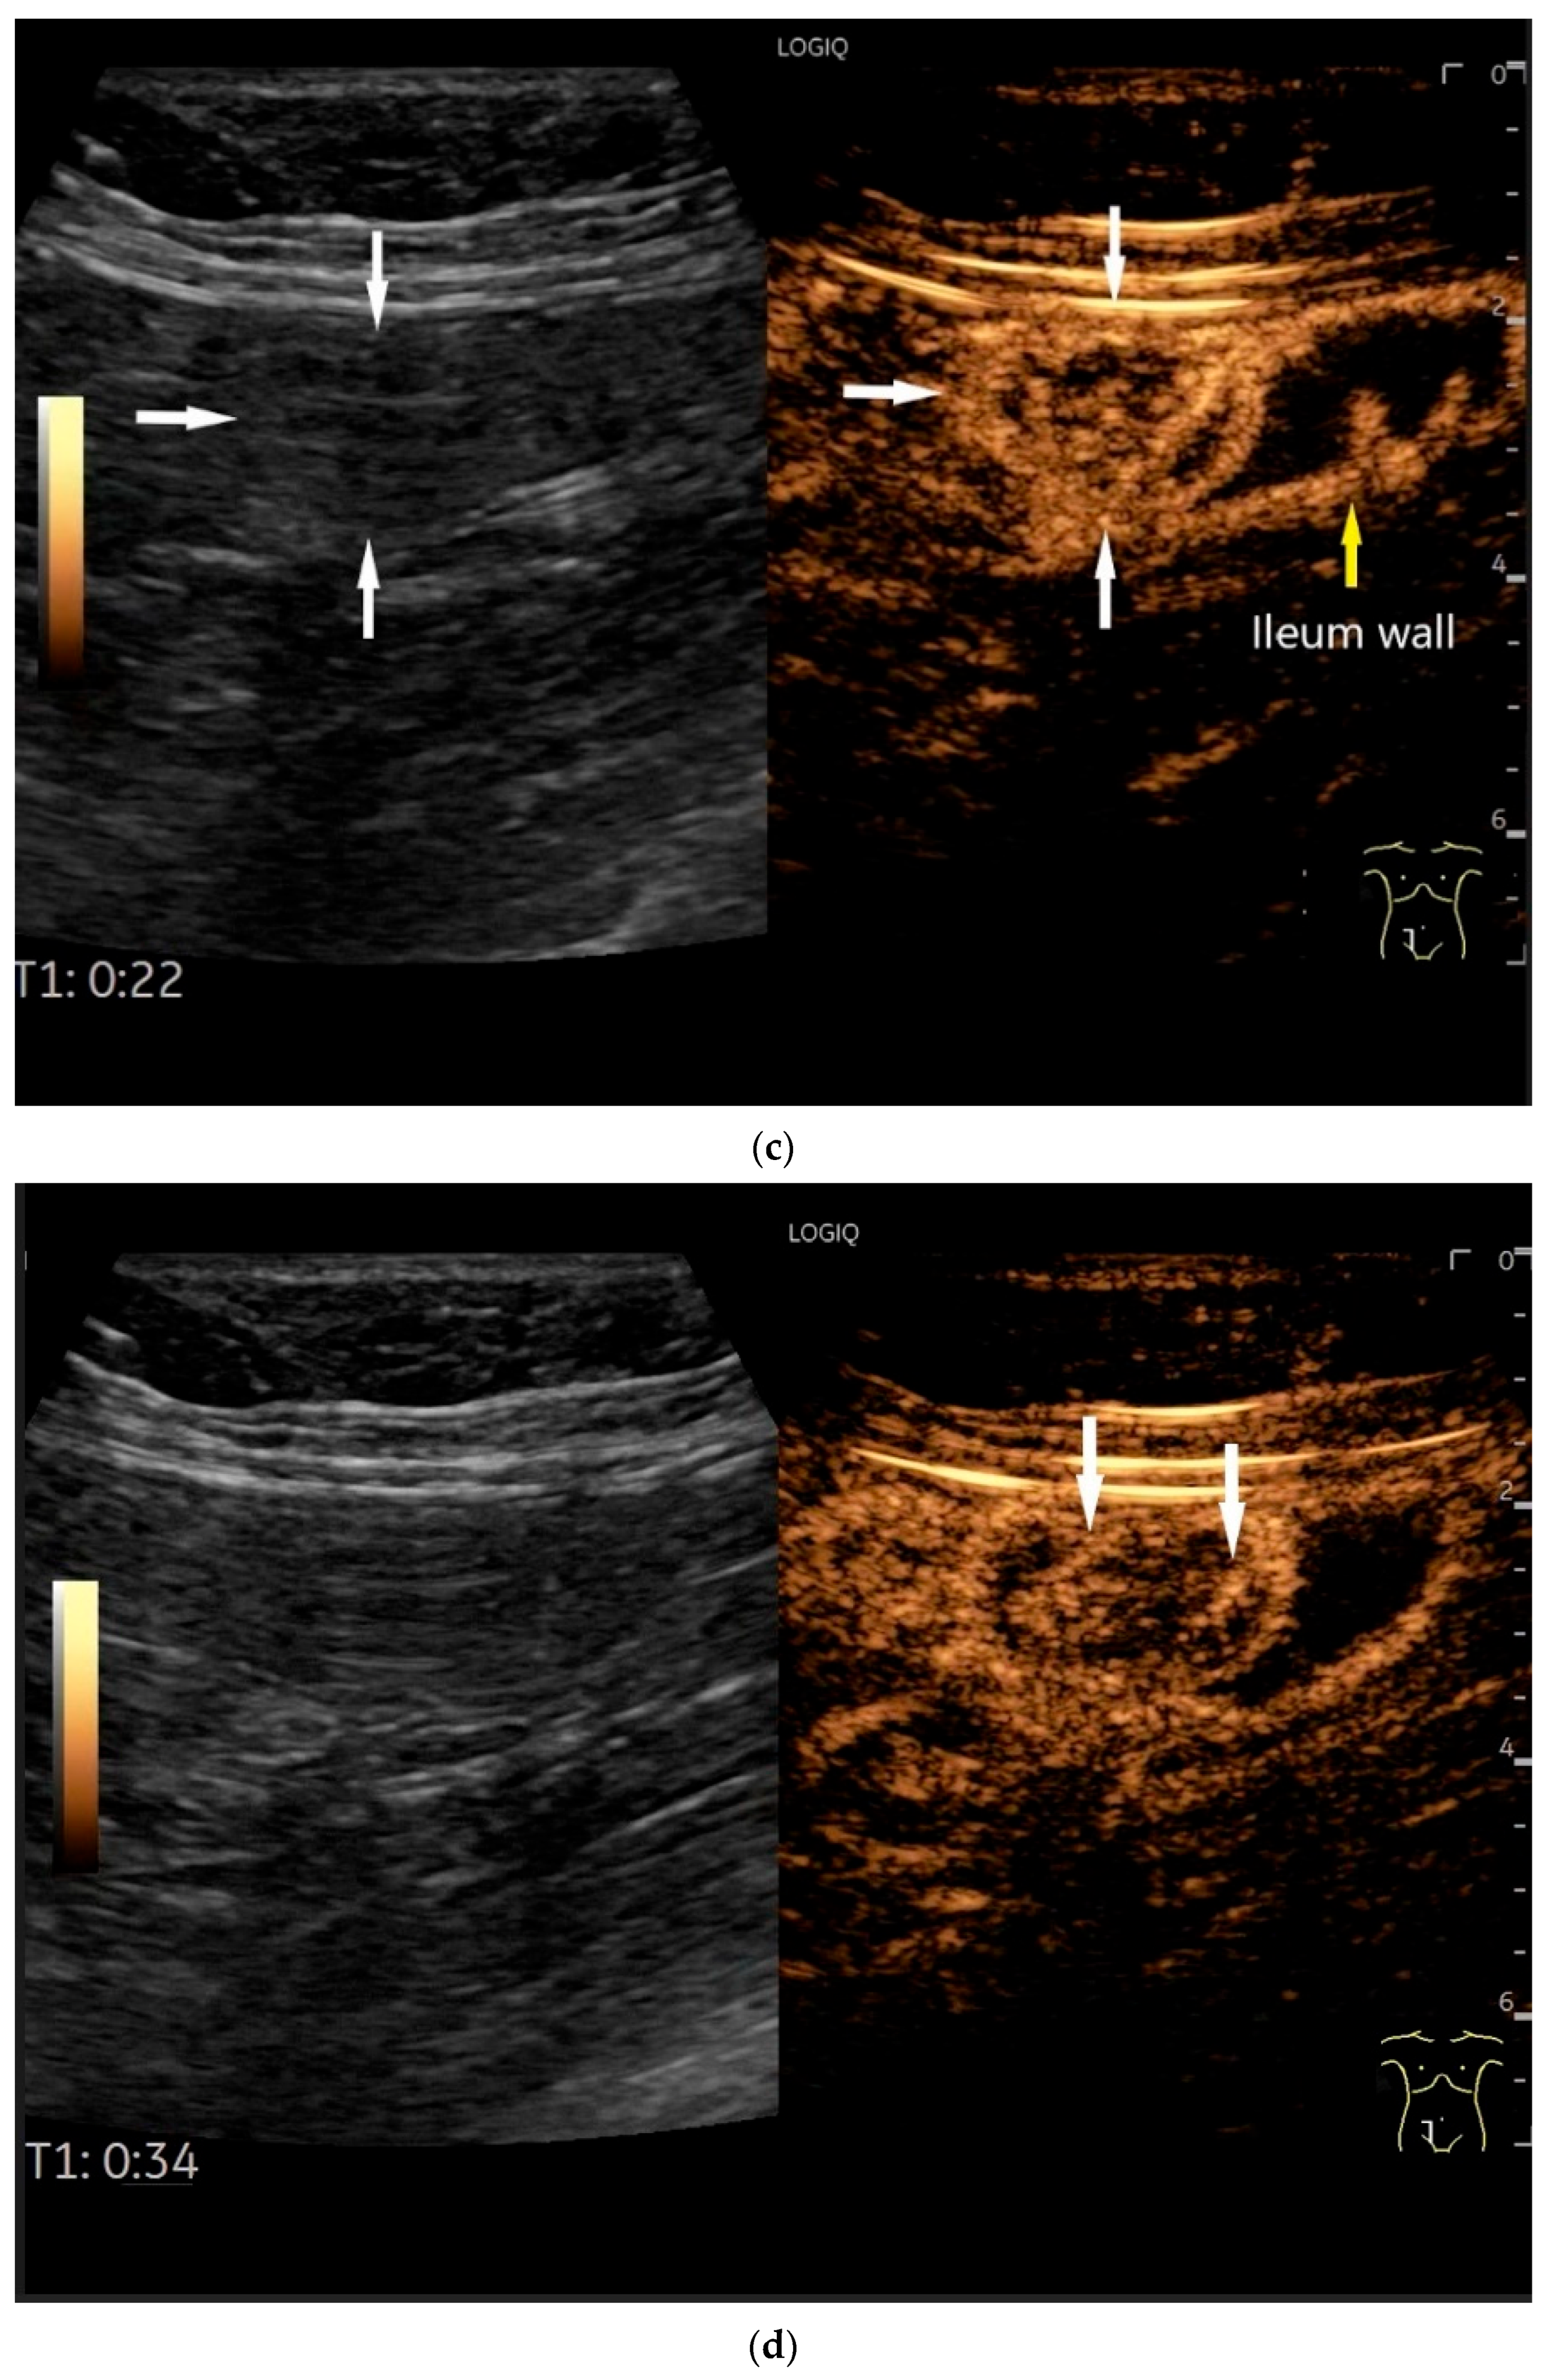

- Cui, N.Y.; Gong, X.T.; Tian, Y.T.; Wang, Y.; Zhang, R.; Liu, M.J.; Han, J.; Wang, B.; Yang, D. Contrast-enhanced ultrasound imaging for intestinal lymphoma. World J. Gastroenterol. 2021, 27, 5438–5447. [Google Scholar] [CrossRef]

| Lymphoma | Very pronounced wall thickening with marked hypoechogenicity. Large regional and distant lymph nodes. Look for splenic infiltration. Tumor vessels on CDI and hyperenhancement on CEUS. Heterogeneous hyperechogenicity of the mesentery with walling of the mesenteric vessels. Multiple localizations are possible. |

- Hasaballah, M.; Abdel-Malek, R.; Zakaria, Z.; Marie, M.S.; Naguib, M.S. Transabdominal ultrasonographic features in the diagnosis of gastrointestinal lymphoma. J. Gastrointest. Oncol. 2018, 9, 1190–1197. [Google Scholar] [CrossRef]

- Goerg, C.; Schwerk, W.B.; Goerg, K. Gastrointestinal lymphoma: Sonographic findings in 54 patients. Am. J. Roentgenol. 1990, 155, 795–798. [Google Scholar] [CrossRef]

- Zhang, X.Y.; Zhang, B.; Cai, S.; Jiang, Y.X.; Li, W.B.; Yang, X.; Zhao, R.N. Ultrasonographic and general pathologic features assessment of small intestinal lymphoma. Zhongguo Yi Xue Ke Xue Yuan Xue Bao 2013, 35, 318–321. [Google Scholar] [CrossRef]